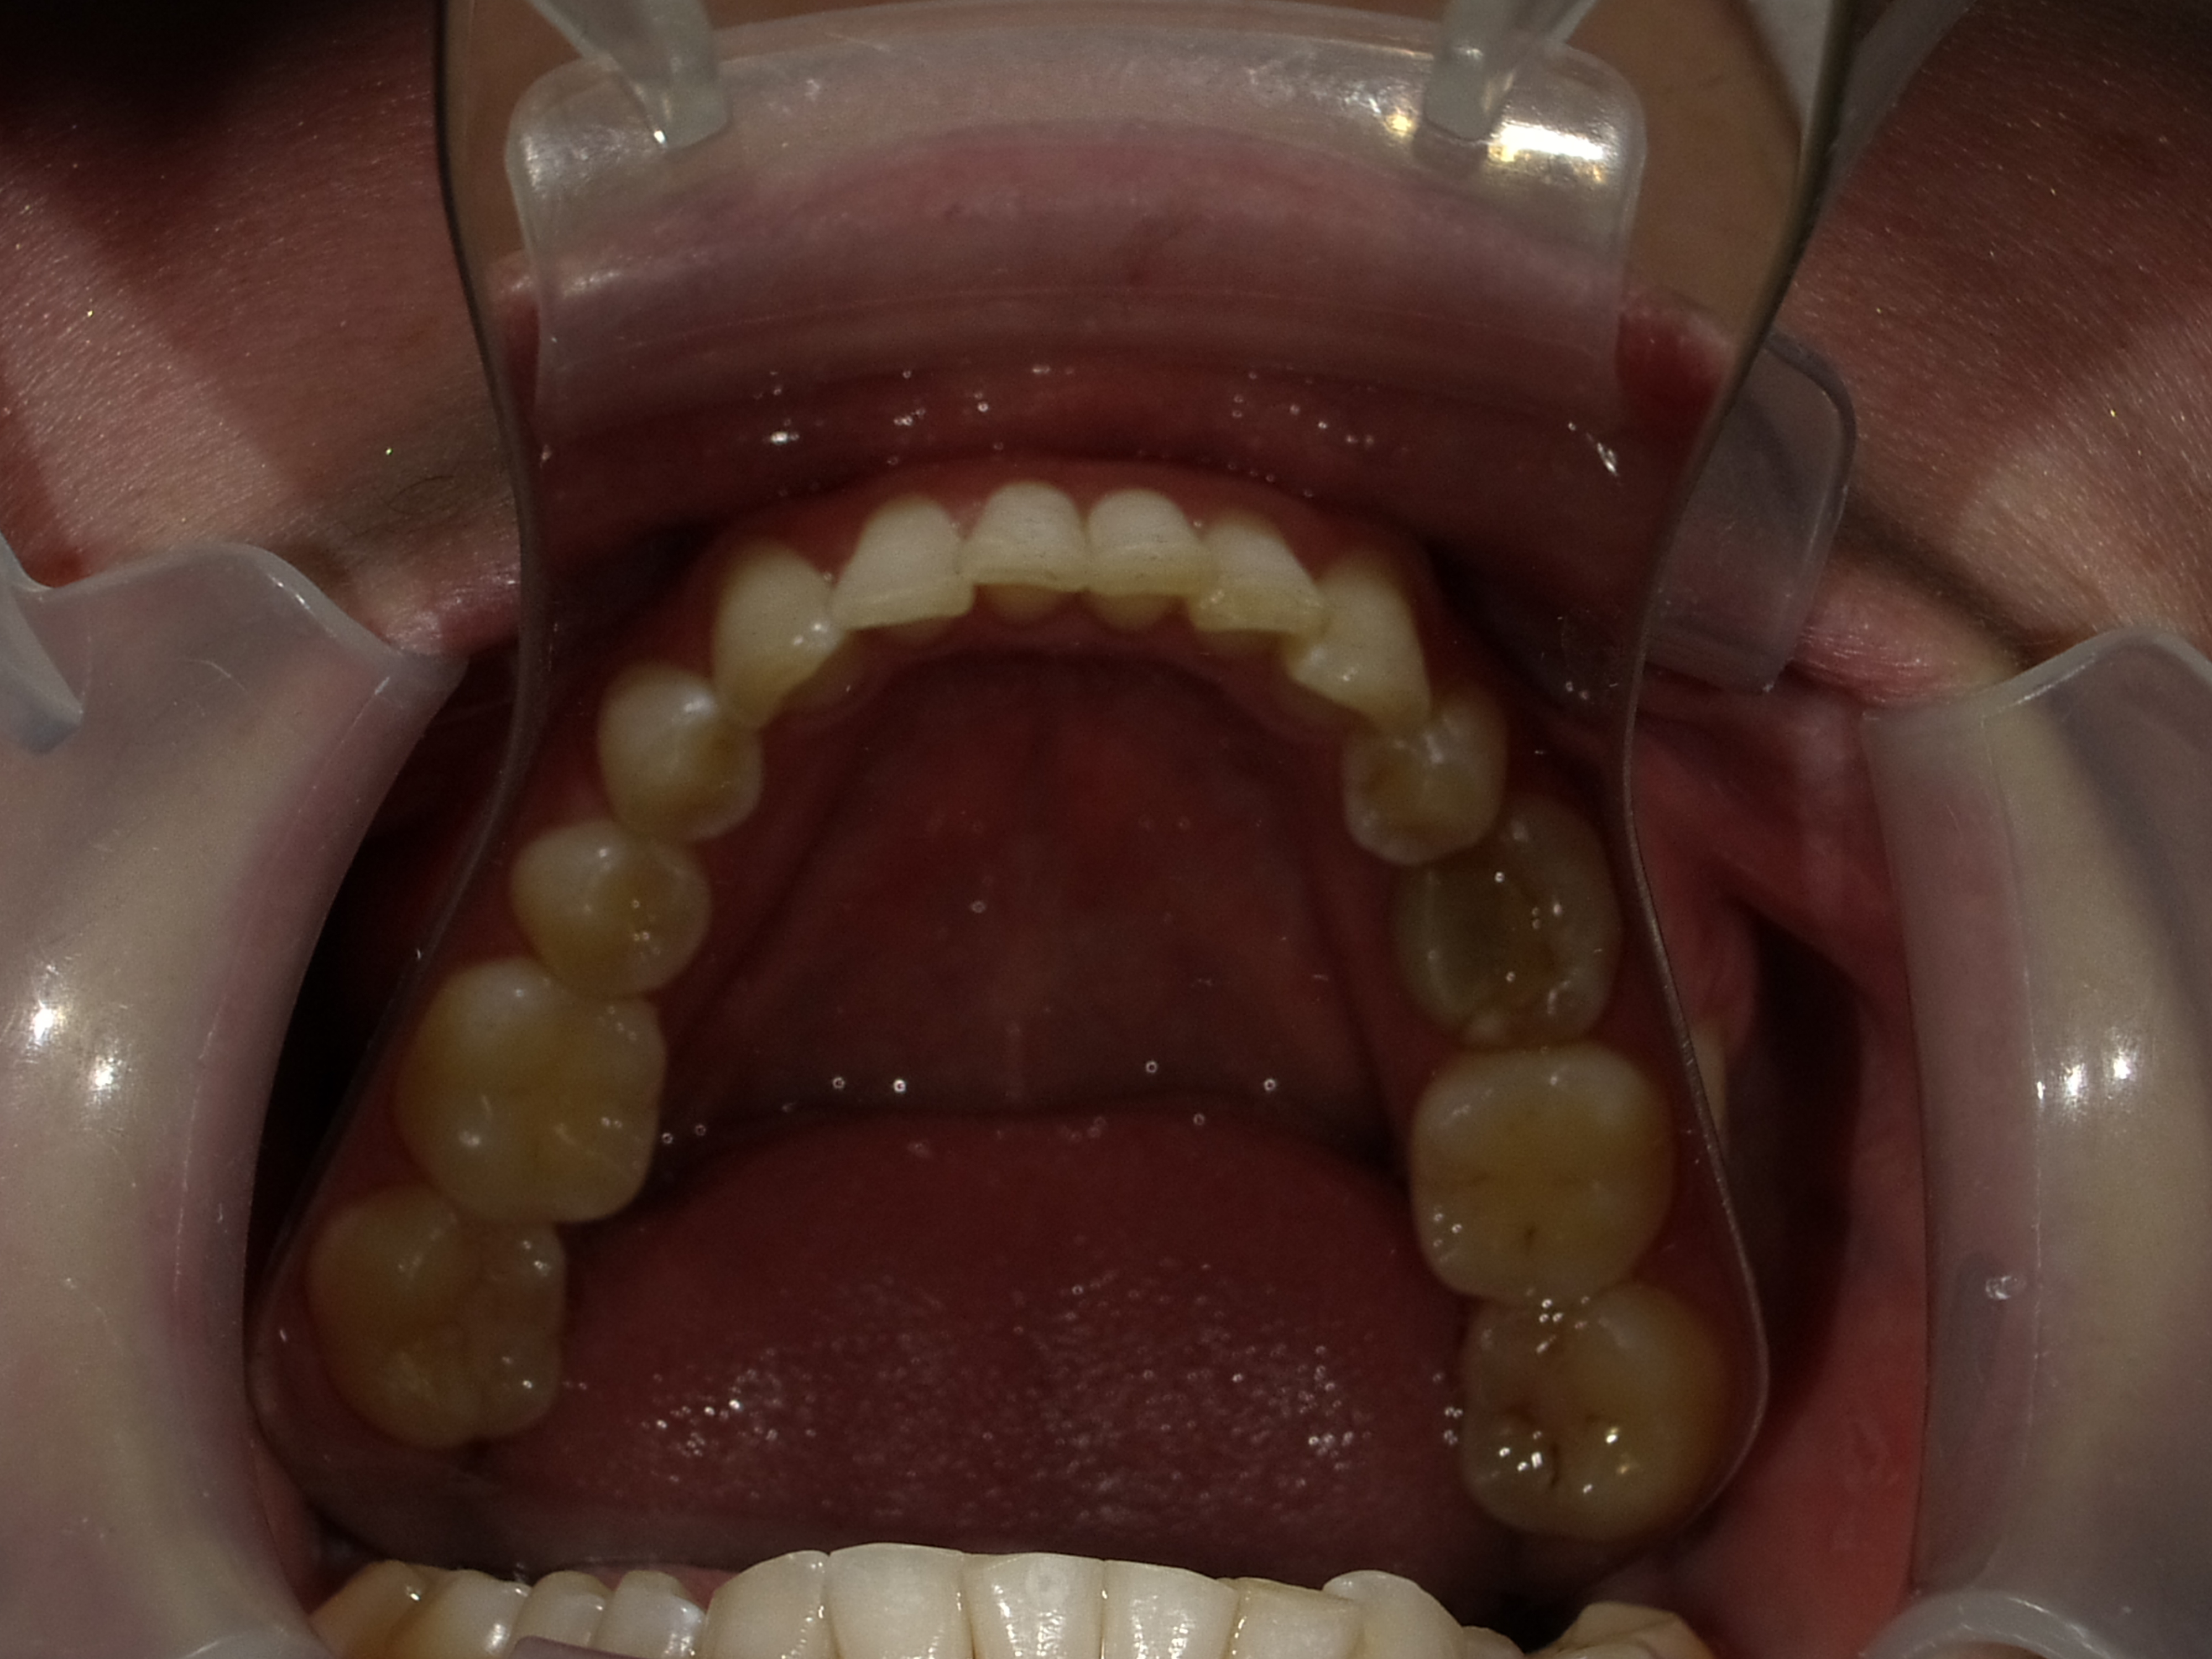

Patient Photographs

At a minimum, 4 photos are required.

3. Maxilary retracted (with mirror is best.

4. Mandibular retracted.

Placeholder Picture